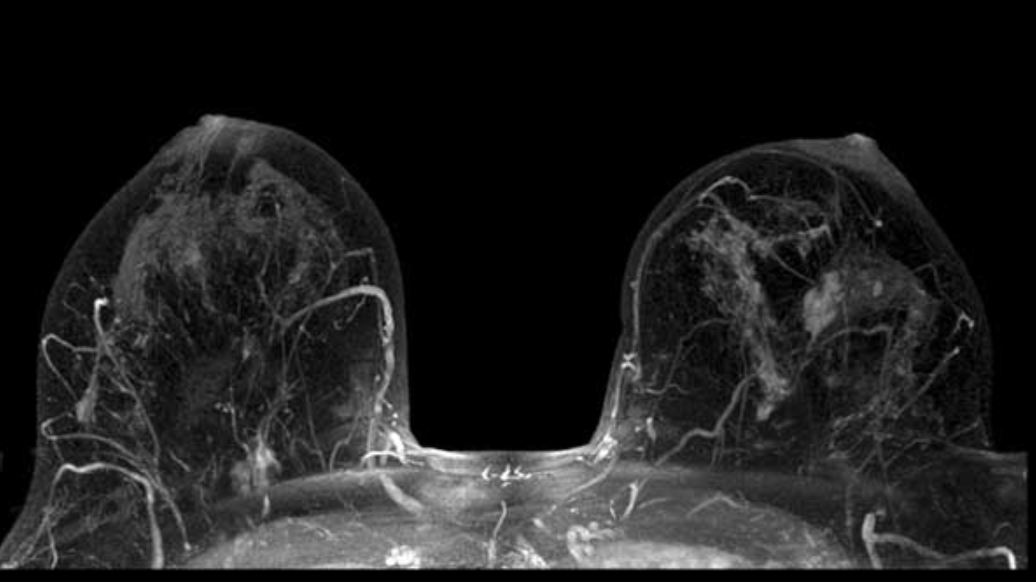

3.5 MRI của vú

MRI có thể được sử dụng với chụp nhũ ảnh để phát hiện ung thư vú, đặc biệt ở những phụ nữ có mô vú dày đặc hoặc những người có nguy cơ mắc bệnh cao.